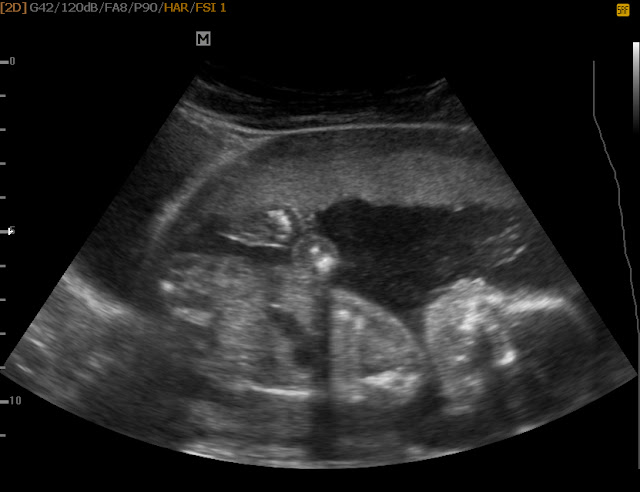

Tak, ultrazvuk kdy už by mohlo být něco vidět proběhl 23.12, asi nejvtipnější návštěva gynekologa za mé éry těhotenství a půl. Šla s námi ještě naše kamarádka a Maxíček samozřejmě. Když jsem šla na řadu, náš brouček provedl zkoušku co dokáže udržet plínka a celkem malá čekárna se stala místností pro plynové masky. Můj statečný muž se tedy ujal zachránit všechny kolem. ~ asi vám nemusím říkat ten pech, že jsem vzala jen jednu plínu navíc, kterou v průběhu boje s tatínkem náš miláček lehce počůral ještě než mu jí nasadil, no maminka v tu chvíli na odstřel ~

Nicméně, možnost podívat se na naší druhou ratolest tedy vyhrála kamarádka, pro kterou to byl poprvé zážitek. A je to tu, pan doktor zkoumá, hledá, zvětšuje, zmenšuje a vypadá na to, že nic moc nevidí. Ultrazvuk zakončil slovy, že mi nic napsat nemůže, protože si vůbec není ani trochu jistej a rozhodně nechce riskovat, že si pak na něj někdo počká venku s "bejsbolkou" když to řekne špatně. Jelikož jsem odmítala říct své 30 členné rodině, která se k nám chystala 26.12, že je to prostě dítě jak mi poradil, začaly jsme přemlouvat. Po chvíli z něj vypadlo, že to ví tak na 75%, což mi naprosto stačilo. Po půl hodině úsměvného přemlouvání a vyprávění historek ~ myslím, že nás slyšeli i lidé o barák vedle ~ jsem dostala obálku. :)

17.1 jsem šla na kontrolu s tím, že mi pan doktor toho pinďu potvrdí na 100%, ale co se k mému překvapení nestalo? Vše je jinak a nyní se do vedení na 75% dostává pinďula holčička. :) ~ nebojte, dort už jsme nedělali :) ~ Takže je to víc napínavé než jsme čekali, jsem zvědavá kdo to bude za měsíc, můžeme dát sázky. :) Můj manžel to okomentoval se slovy: "Já si to myslel, to jen potvrzuje Tvou nynější úchylnost na růžovou barvu a těch pár, asi 100, pupínků na obličeji" :D no není to miláček? :)

Nyní je tedy situace jasně růžová, hned po dalším ultra dám info. Hlavně aby mě pan doktor nepřekvapil a neřekl, tak to bude holka, ale i kluk maminko, máte je tam oba. No to by mi těch pupínků naskočilo asi trochu víc. :)